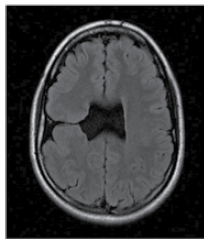

Menino de 3 anos de idade apresenta hemiparesia à esquerda e epilepsia focal. Estudo de imagem por ressonância magnética revela alteração a seguir.

O achado de imagem é compatível com o diagnóstico de